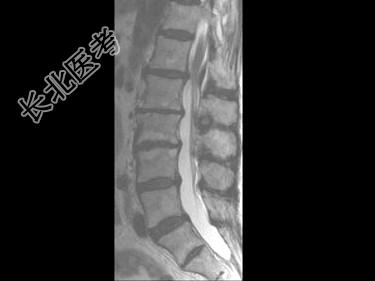

- 单项选择题男,59岁, 硬膜外麻醉后背痛1周余,结合MRI检查, 最可能的诊断是 ( )

E、硬膜外血肿